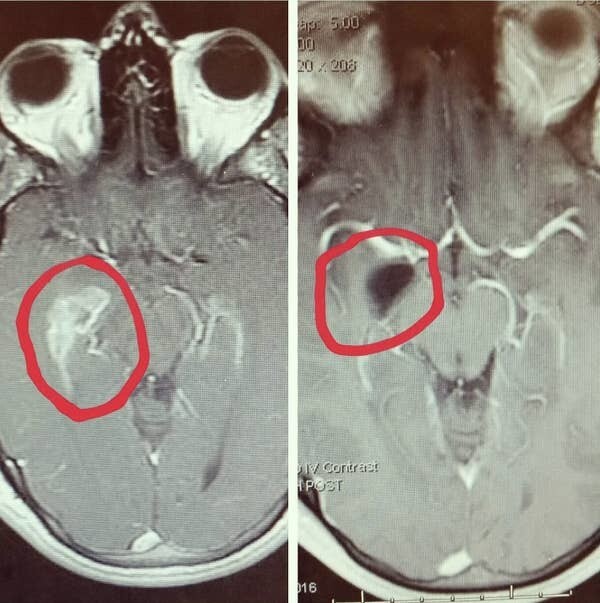

7. Старый медицинский журнал, в котором изображена пациентка до и после удаления опухоли в XVII веке

8. МРТ мозга человека до и после операции по удалению опухоли в височной доле